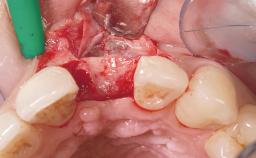

Soft Tissue Grafting Simultaneous

Soft Tissue Anatomy Intact Defective